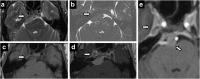

Meckel's cave is a dural recess in the posteromedial portion of the middle cranial fossa that acts as a conduit for the trigeminal nerve between the prepontine cistern and the cavernous sinus, and houses the Gasserian ganglion and proximal rootlets of the trigeminal nerve. It serves as a major pathway in perineural spread of pathologies such as head and neck neoplasms, automatically upstaging tumours, and is a key structure to assess in cases of trigeminal neuralgia. The purpose of this pictorial review is threefold: (1) to review the normal anatomy of Meckel's cave; (2) to describe imaging findings that identify disease involving Meckel's cave; (3) to present case examples of trigeminal and non-trigeminal processes affecting Meckel's cave.

Teaching points: • Meckel's cave contains the trigeminal nerve between prepontine cistern and cavernous sinus. • Assessment is essential for perineural spread of disease and trigeminal neuralgia. • Key imaging: neural enhancement, enlargement, perineural fat/CSF effacement, skull base foraminal changes.